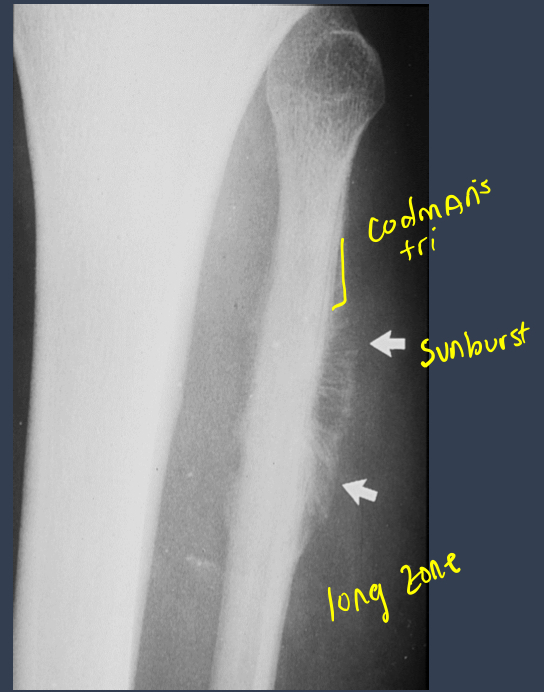

what is this?

osteosarcoma

MC location for Ewing’s sarcoma?

diaphysis of humerus and femur

Local P and swelling.

Systemic signs: fever, anemia, increased ESR.

Ewing sarcoma